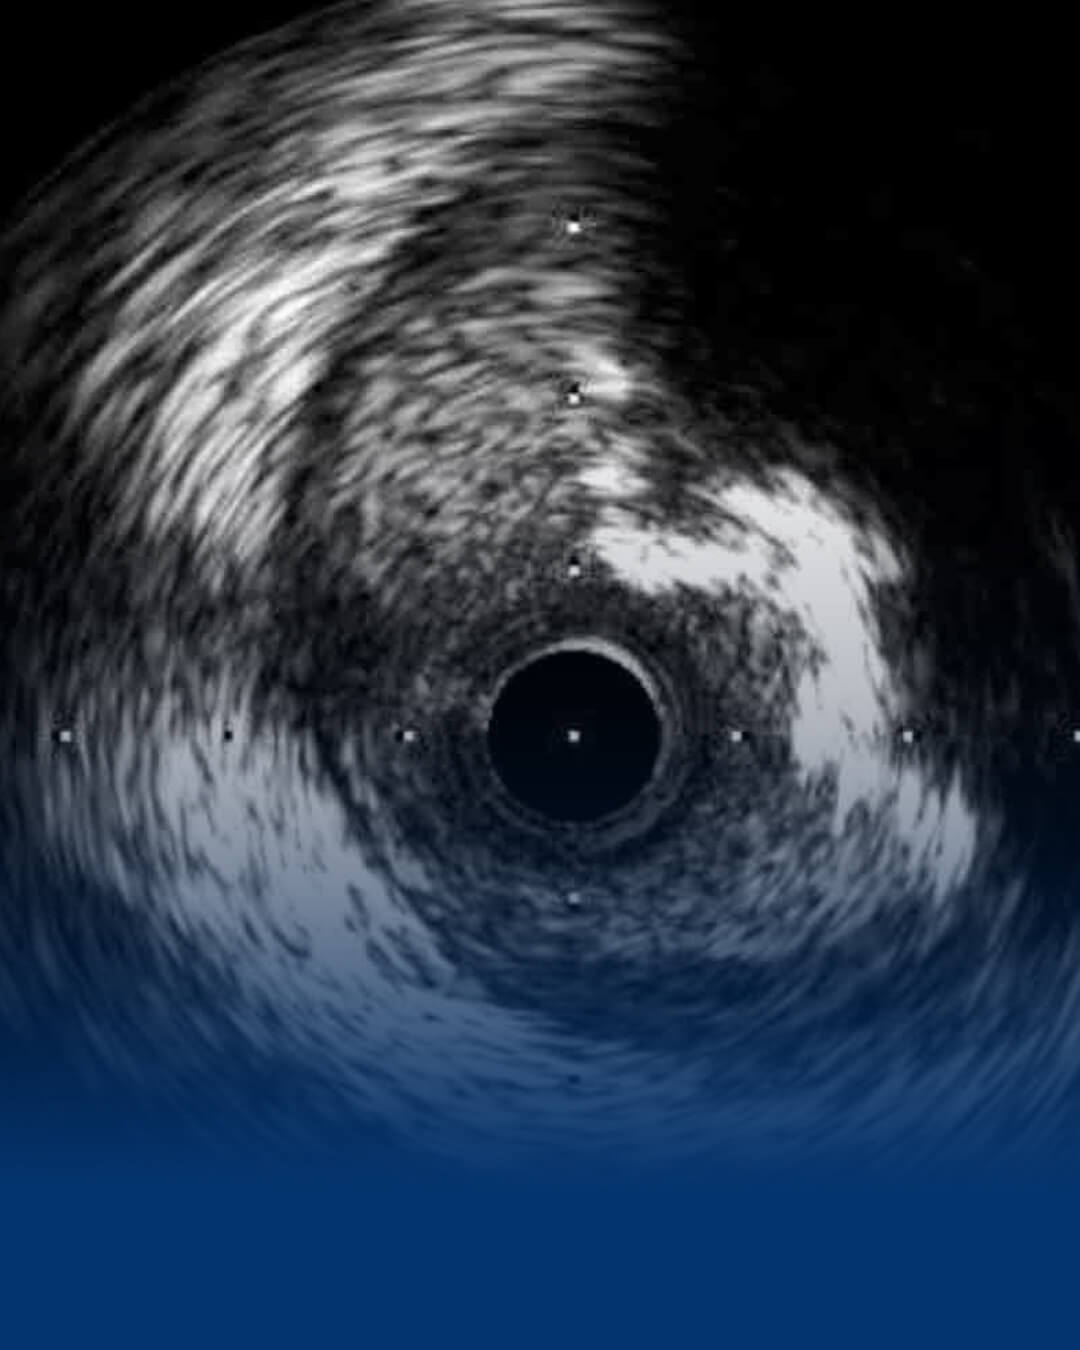

Kalp sağlığınızda modern ve bilimsel yaklaşımlar. Kompleks koroner damar tıkanıklıkları, ameliyatsız kapak değişimleri (TAVI) ve ileri girişimsel kardiyoloji yöntemleriyle sağlığınızı uzman ellere emanet edin.

Akademik birikimi ileri girişimsel yöntemlerle birleştiriyoruz.

Kalp sağlığı, girişimsel kardiyoloji yöntemleri ve ameliyatsız tedavi süreçleri hakkında merak edilenleri uzman bakış açısıyla izleyin.